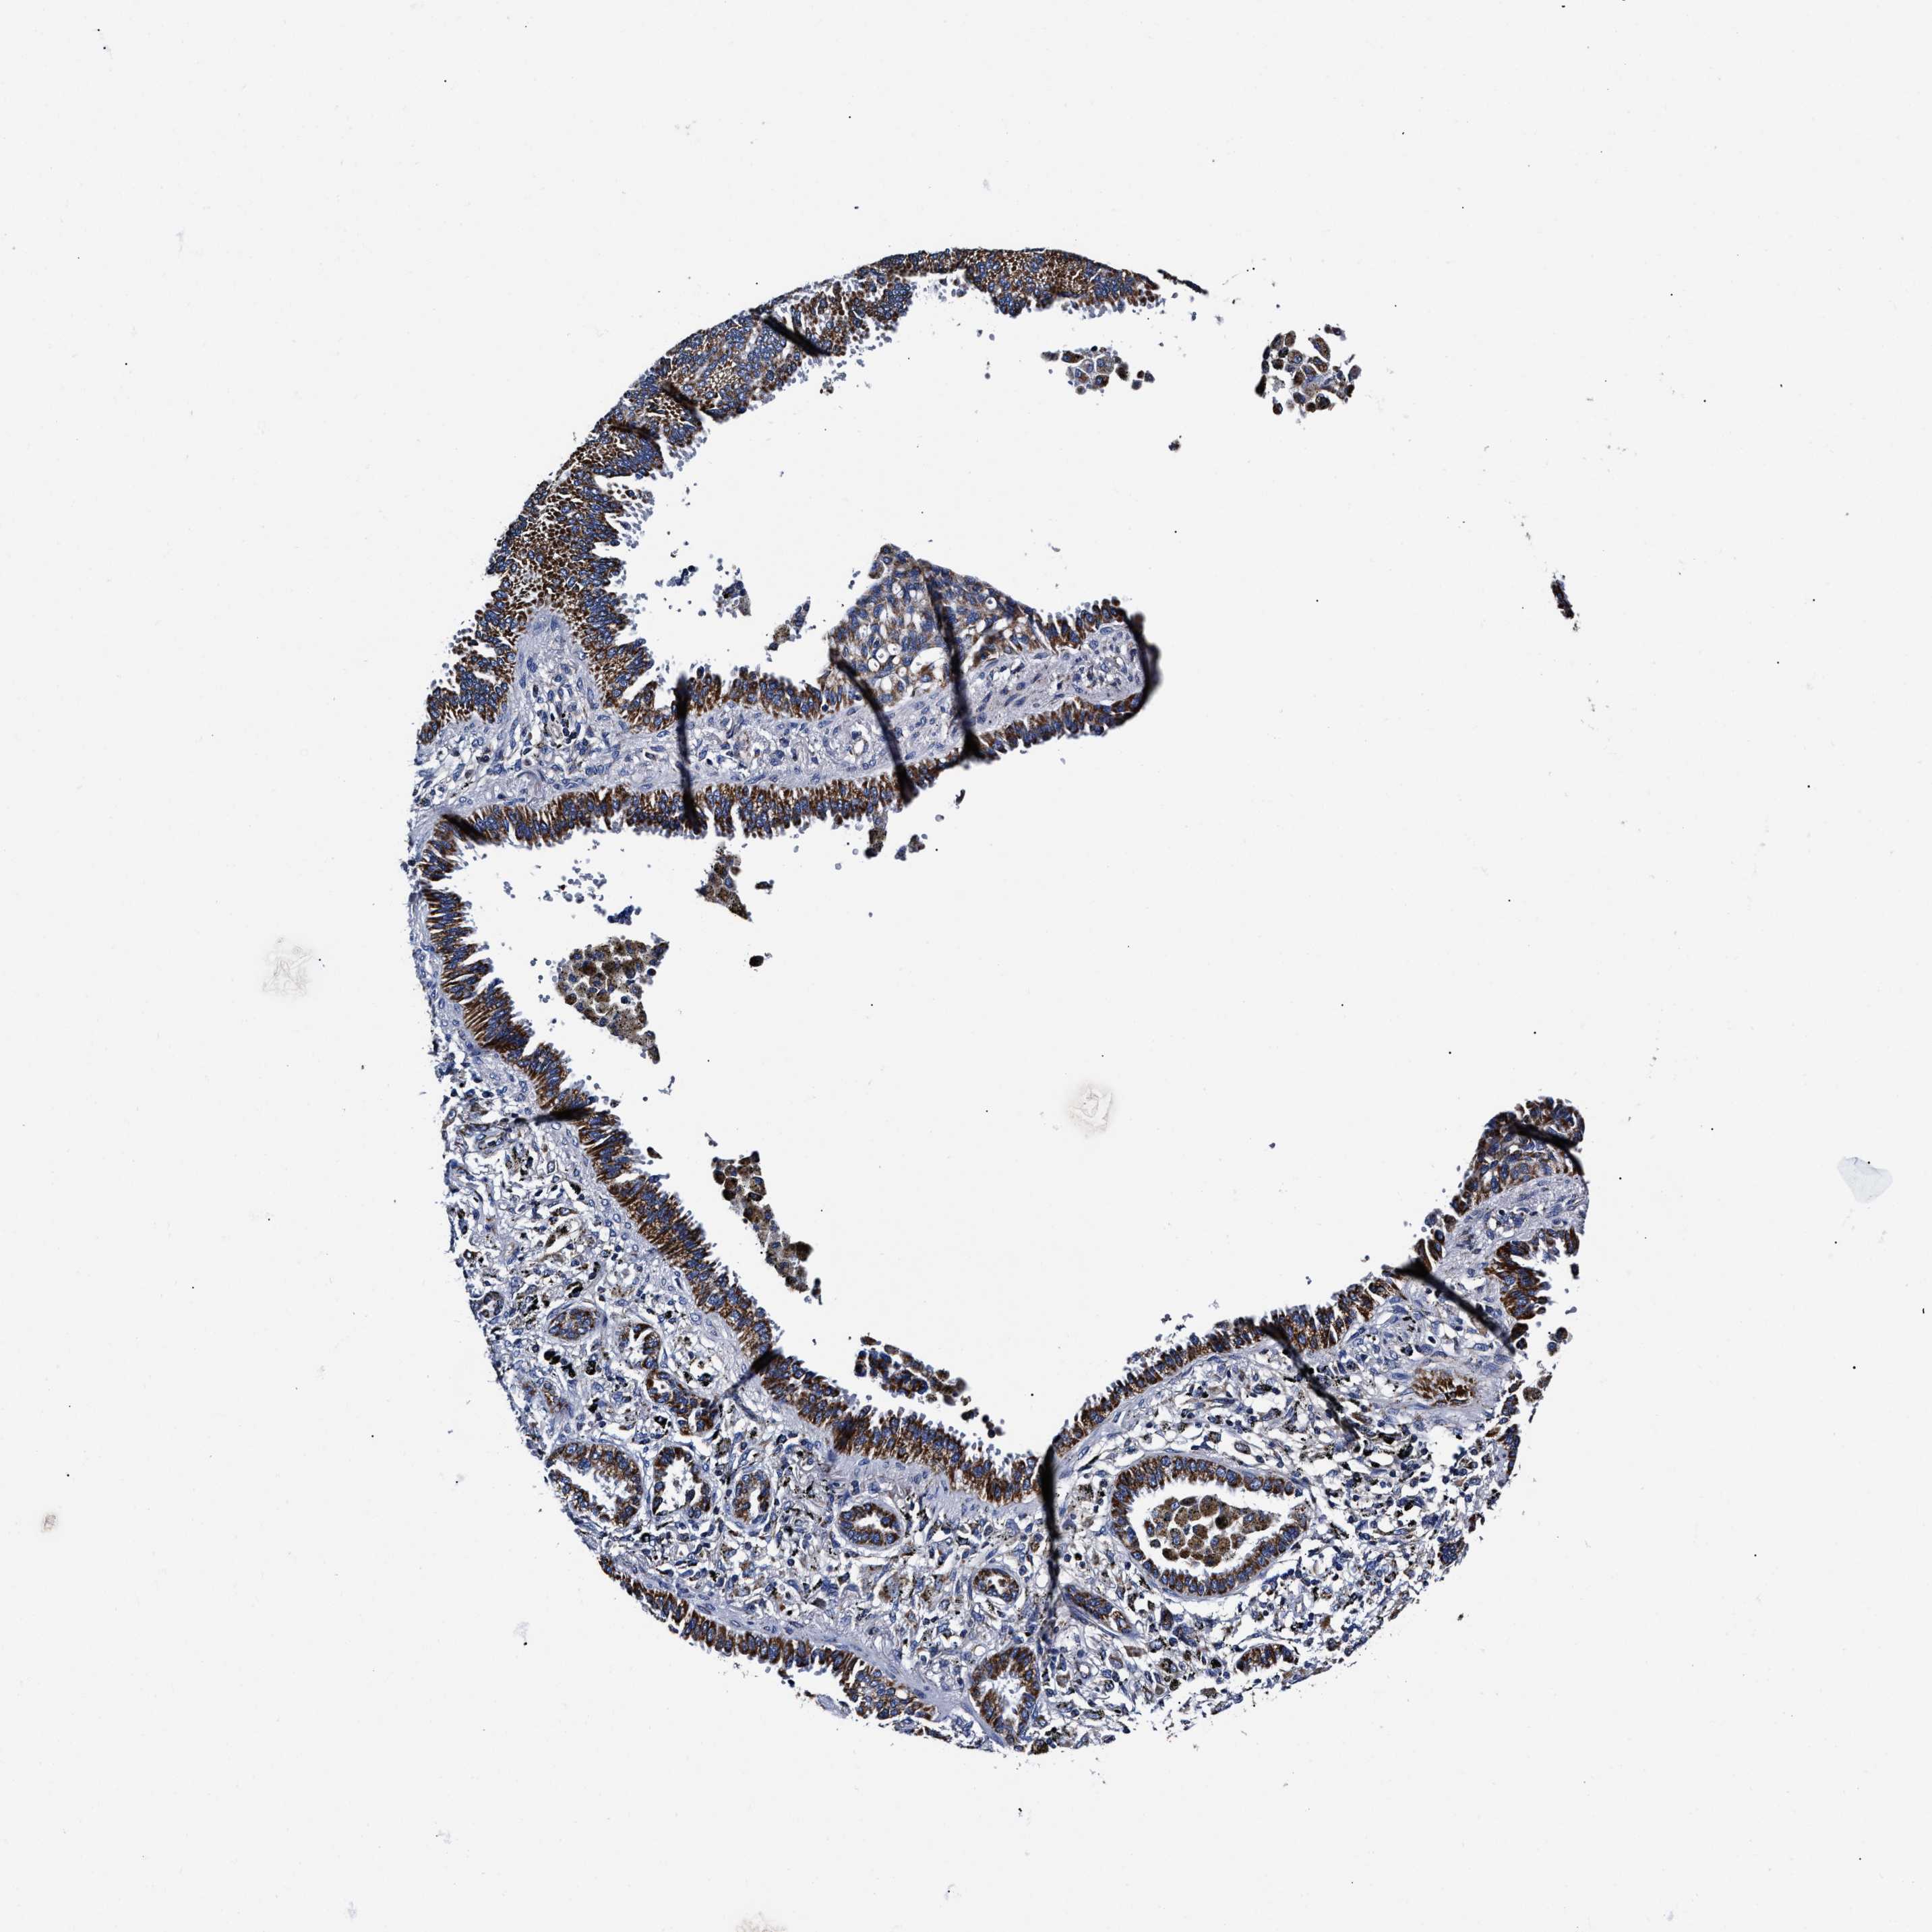

LUNG ADENOCARCINOMA (VALIDATION) - Interactive survival scatter ploti

The Survival Scatter plot shows the clinical status (i.e. dead or alive) for all individuals in the patient cohort, based on the same data that underlies the corresponding Kaplan-Meier plots. Patients that are alive at last time for follow-up are shown in blue and patients who have died during the study are shown in red.

The x-axis shows the expression levels (FPKM) of the investigated gene in the tumor tissue at the time of diagnosis. The y-axis shows the follow-up time after diagnosis (years). Both axes are complimented with kernel density curves demonstrating the data density over the axes. The top density plot shows the expression levels (FPKM) distribution among dead (red) and alive patients (blue). The right density plot shows the data density of the survived years of dead patients with high and low expression levels respectively, stratified using the cutoff indicated by the vertical dashed line through the Survival Scatter plot. This cutoff is automatically defined based on the FPKM cutoff that minimizes the p-score. The cutoff can be changed by dragging the vertical line or by entering a cutoff value in the square labeled "Current cut-off".

Under the Survival Scatter plot the p-score landscape (black curve; left axis) is shown together with dead median separation (red curve; right axis). Dead median separation is the difference in median mRNA expression between patients who have died with high and low expression, respectively. It is calculated as follows: median FPKM expression of dead patients with high expression - median FPKM expression of dead patients with low expression. This is intended to aid the user in visually exploring custom cutoffs and the associated p-scores and dead median separation.

Individual patient data is displayed and can be filtered by clicking on one or more of the category buttons on the top of the page. Categories describing expression level and patient information include: high, low, alive, dead, female, male and tumor stages. The scale of the x-axis can be toggled between linear and log-scale by clicking on the "x log" button. Mouse-over function shows TCGA ID, patient information and mRNA expression (FPKM) for each patient.

& Survival analysisi

Kaplan-Meier plots summarize results from analysis of correlation between mRNA expression level and patient survival. Patients were divided based on level of expression into one of the two groups "low" (under cut off) or "high" (over cut off). X-axis shows time for survival (years) and y-axis shows the probability of survival, where 1.0 corresponds to 100 percent.

HINT2 is not prognostic in Lung Adenocarcinoma (validation)

: 23.38

P scorei

N/A

Average pTPM 33.0

Number of samples 105